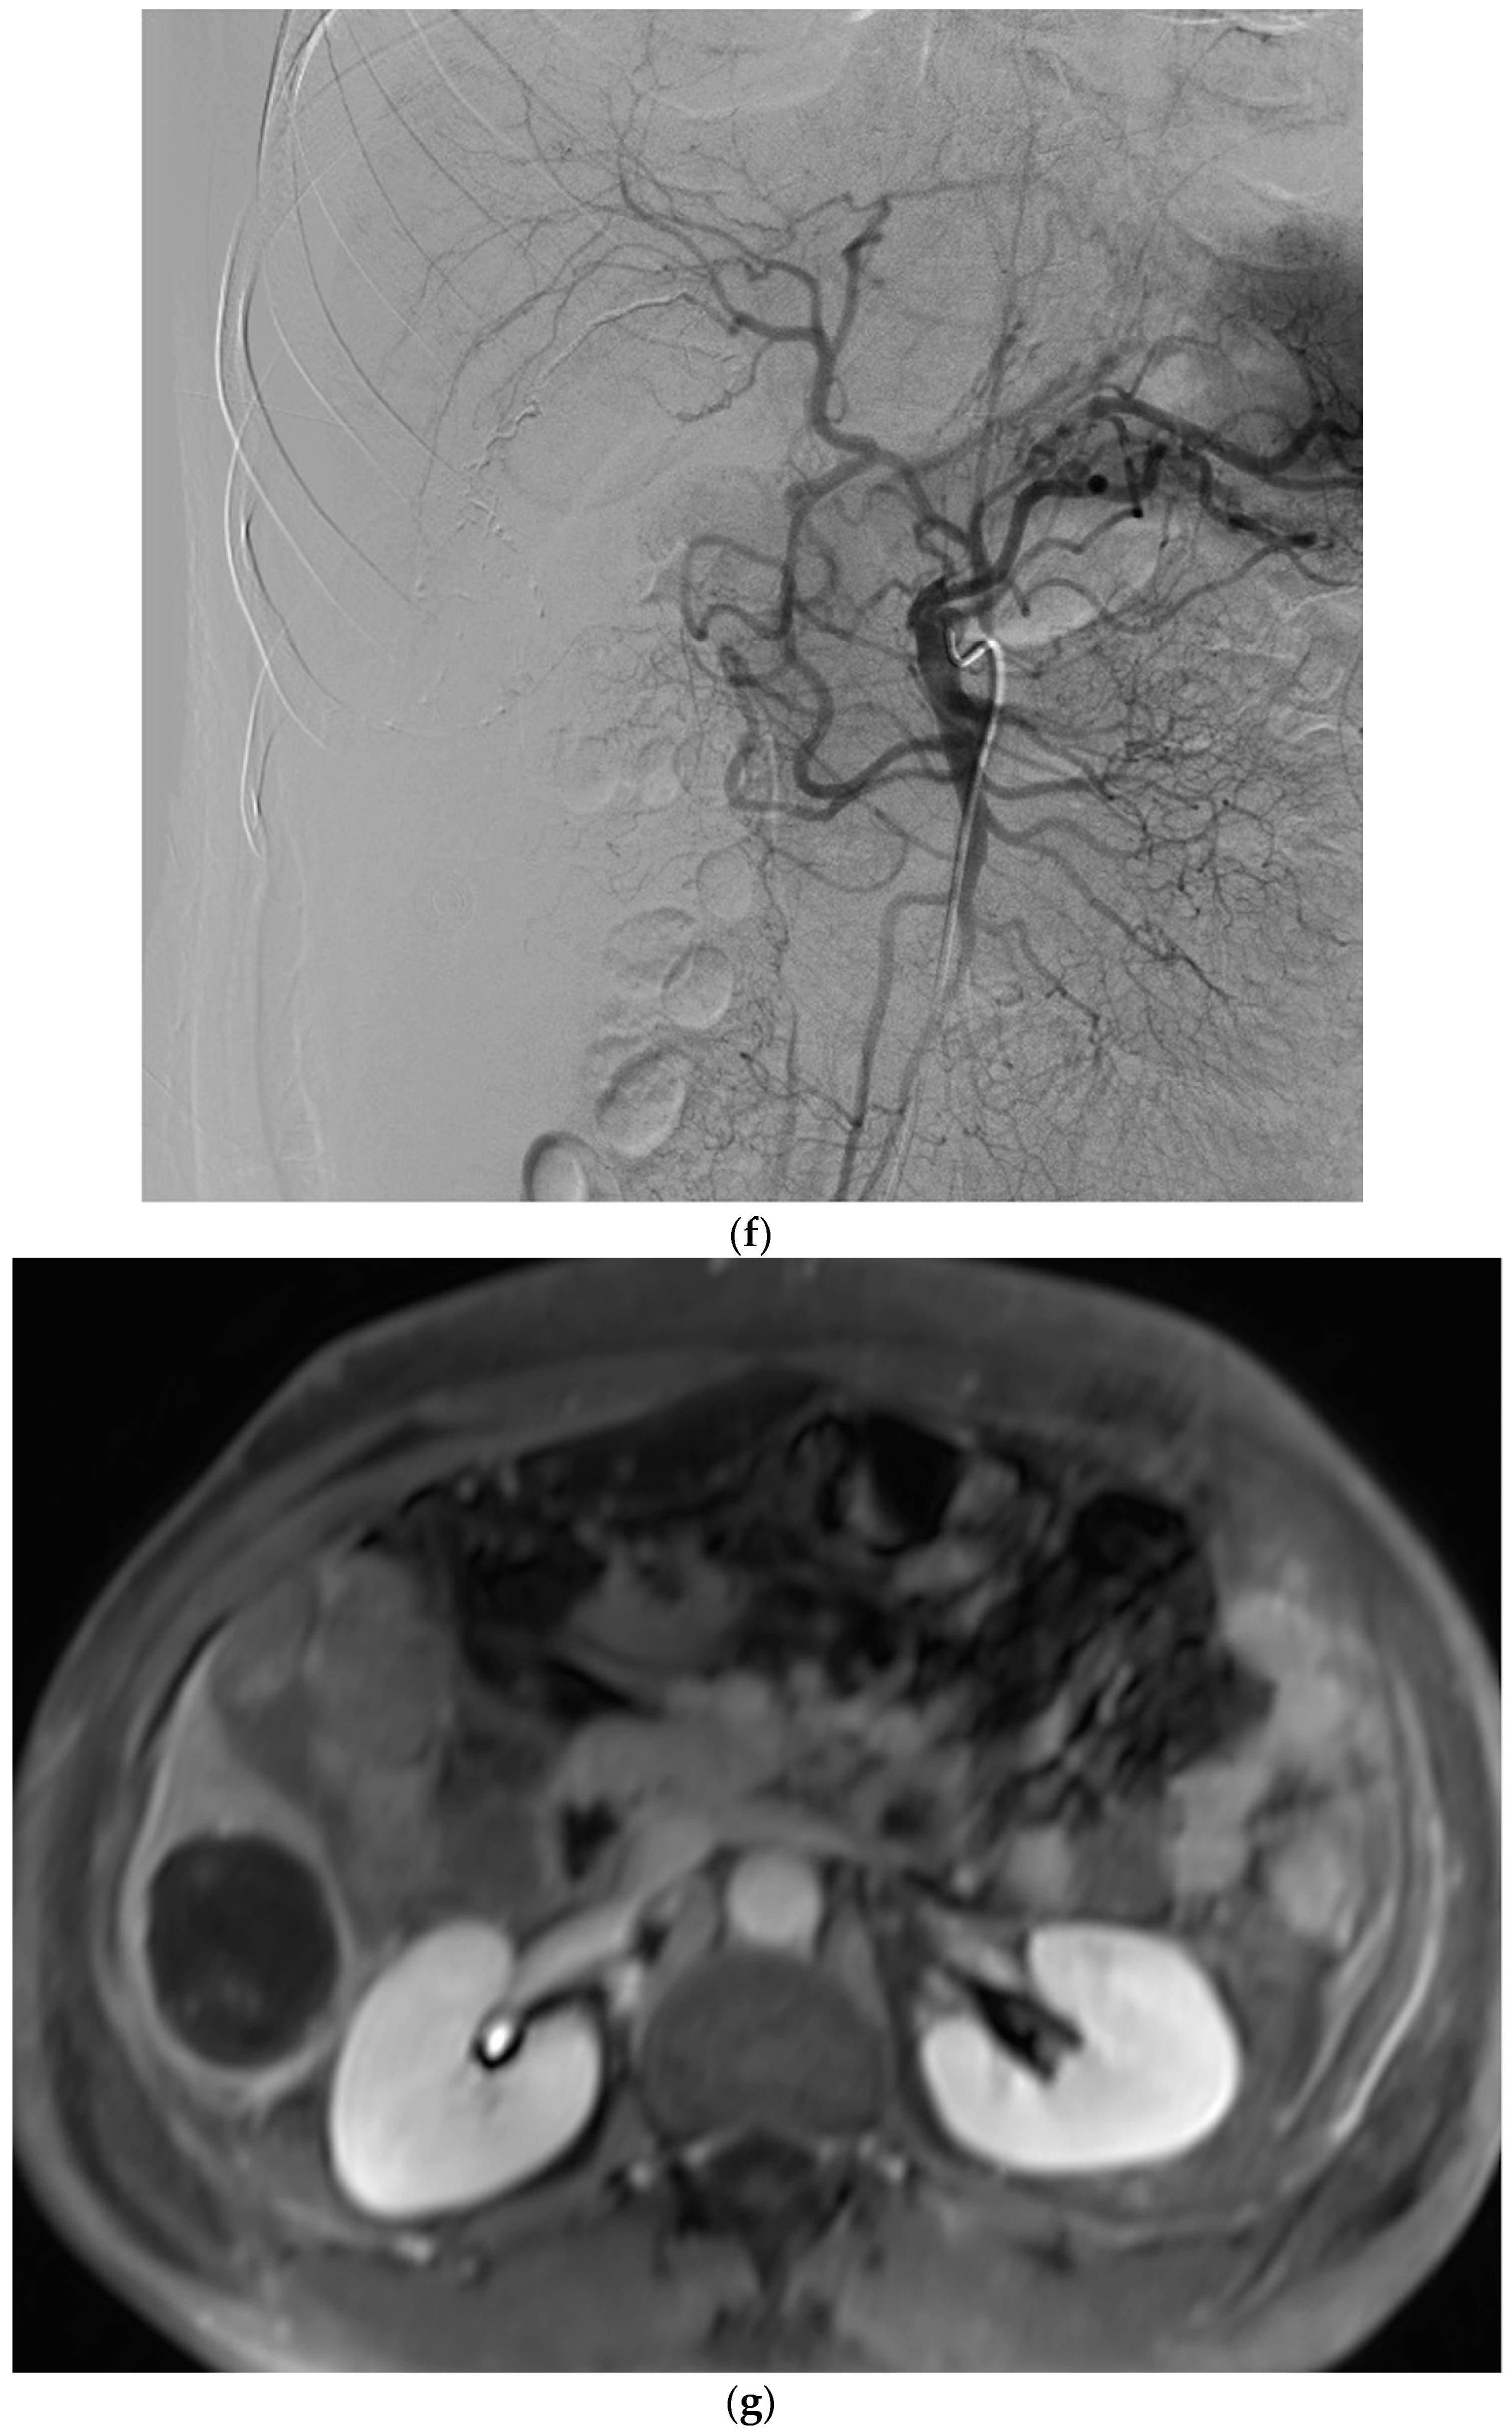

2.4. Selective Arterial Embolization Procedure